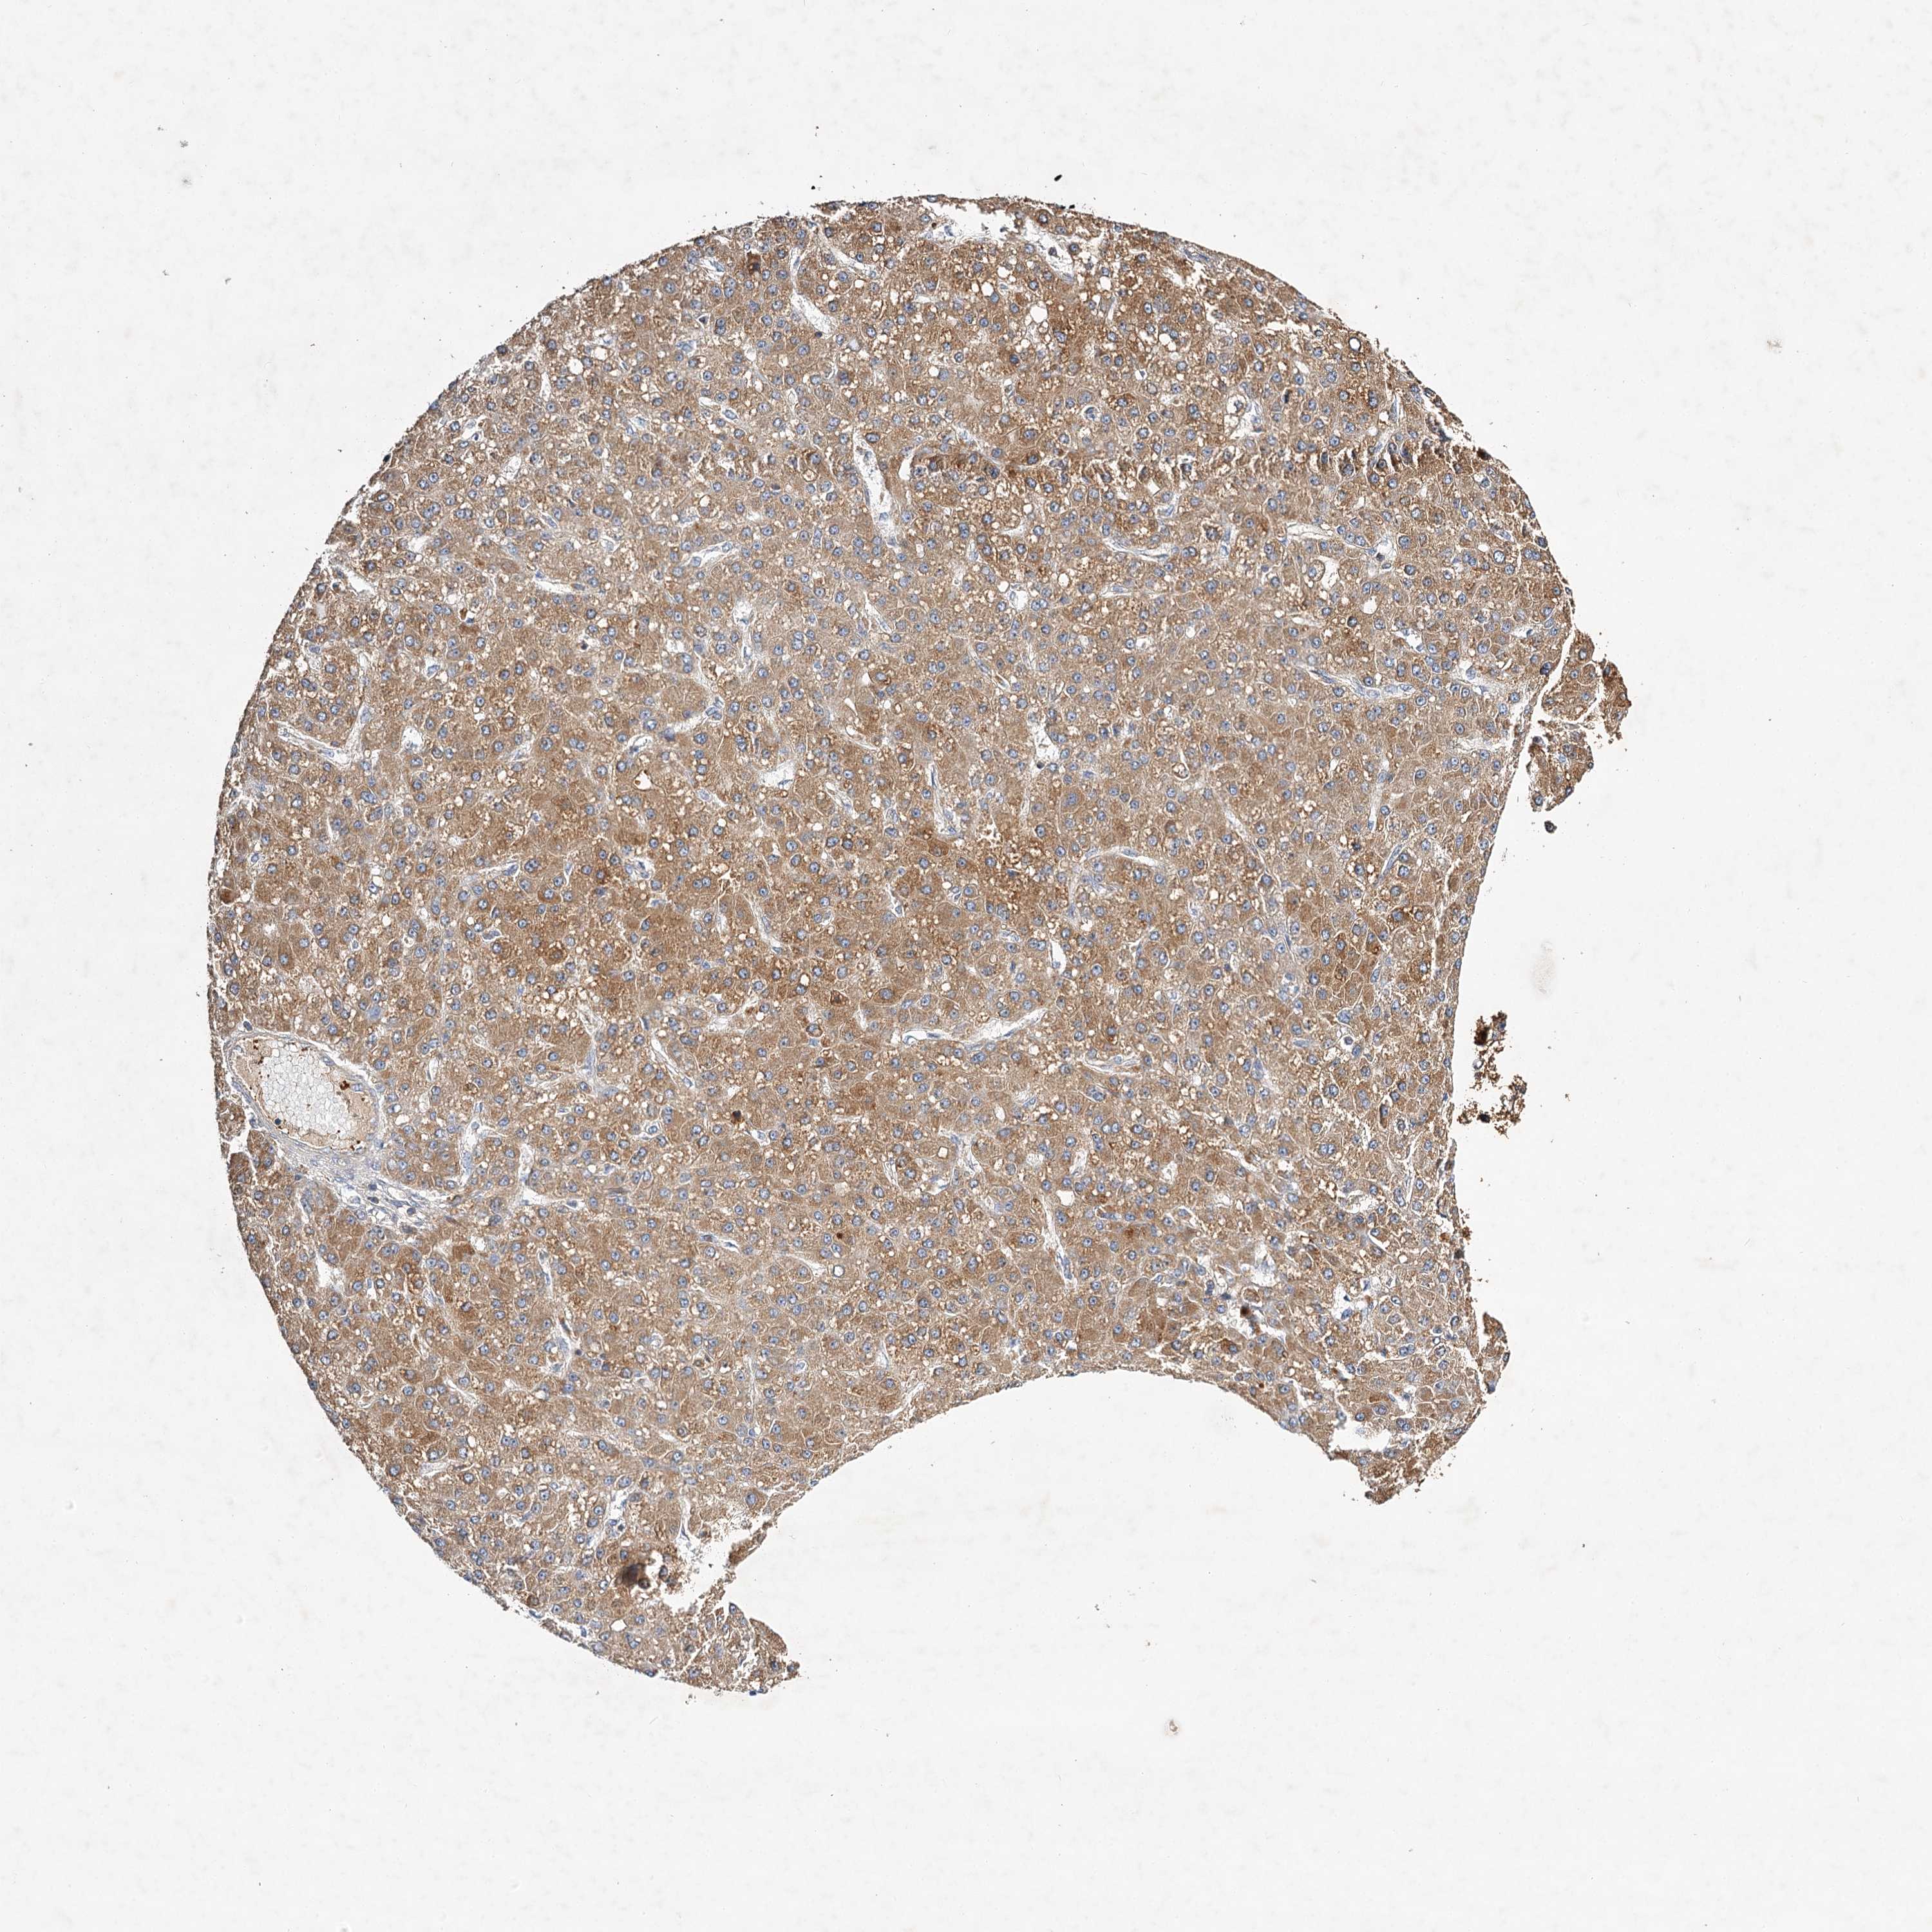

LIVER CANCER - Protein expressioni

A mouse-over function shows sample information and annotation data. Click on an image to view it in a full screen mode. Samples can be filtered based on level of antibody staining by selecting one or several of the following categories: high, medium, low and not detected. The assay and annotation is described here.

Note that samples used for immunohistochemistry by the Human Protein Atlas do not correspond to samples in the TCGA dataset.

Antibody stainingi

Antibody staining in the annotated cell types in the current human tissue is reported as not detected, low, medium, or high, based on conventional immunohistochemistry profiling in selected tissues. This score is based on the combination of the staining intensity and fraction of stained cells.

Each image is clickable and will lead to virtual microscopy that enables deeper exploration of all samples and also displays staining intensity scores, fraction scores and subcellular localization as well as patient and tissue information for each sample.

Antibody HPA032060

Antibody HPA032062

Antibody CAB034116

Staining

High

Medium

Low

Not detected

Intensity

Strong

Moderate

Weak

Negative

Quantity

>75%

75%-25%

<25%

None

Location

Nuclear

Cytoplasmic/membranous

Cytoplasmic/membranous,nuclear

Cholangiocarcinoma

Carcinoma, Hepatocellular, NOS